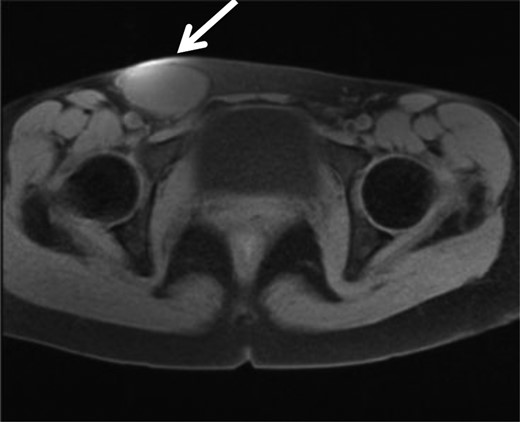

A 35-year-old woman was referred to our hospital for a painful right groin tumor which grew in size which was not related to her menstrual cycle. With the diagnosis of inguinal endometriosis, she had been treated with two cycles of low-dose birth-control pills, and five cycles of genogest previously, but the groin was increased in size to 5-cm with pain. In her past medical history, no history of gynecologic problems and specifically no dysmenorrhea nor dyspareunia were recorded. In the right groin, there was a 5-cm bulge which was detected as a homogeneous hypoechoic subcutaneous tumor and measured 53 × 29 mm by ultrasonography (Fig. 1). Her serum cancer antigen-125 was elevated to 95.4 U/ml (range <35 U/ml) before starting hormone therapy, and down to 40 U/ml when she came to our hospital even though the tumor size was unchanged. Magnetic resonance imaging (MRI) revealed a 6-cm unilocular tumor with internal high intensity in T1WI image which suggested internal bleeding (Fig. 2). We diagnosed the right inguinal tumor as a Nuck cyst. An inguinal approach was selected and after opening the skin and subcutaneous fat, a dark red tumor was founded which protruded from the femoral ring, in spite of our initial impression that the tumor was located along the round ligament (Fig. 3). After careful dissection, the tumor turned to be a unilocular cyst containing serous fluid, which was connected with the peritoneum through a string structure at the femoral ring, which was not connected with the abdominal cavity. The cyst was excised and the string structure was resected at the femoral ring. We inserted a plug into the extended femoral ring, and confirmed no other hernia. Her postoperative course was uneventful, and she was discharged on the first postoperative day. The histopathologic examination showed that mesothelial cells lined the wall of the cyst with degeneration, inflammation, hemorrhage, formation of hyperplastic collagen fiber and hemosiderosis without malignancy (Fig. 4). The immunohistochemistry [Calretinin(+)] confirmed the mesothelial origin of the cyst-lining cells and [CD10(+), ER(+), PgR(+)] suggested the endometrial origin of a few stromal tissue composing the cystic wall. As of 10 months after the operation, no recurrence of hernia or cyst has been encountered.

MRI showed a high intensity tumor in T1WI which suggest bleeding in the tumor, in the right inguinal region.